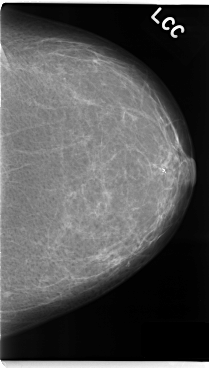

C_0131_1.LEFT_CC

LEFT_CC LINES 4776 PIXELS_PER_LINE 2712 BITS_PER_PIXEL 12 RESOLUTION 50 NON_OVERLAY